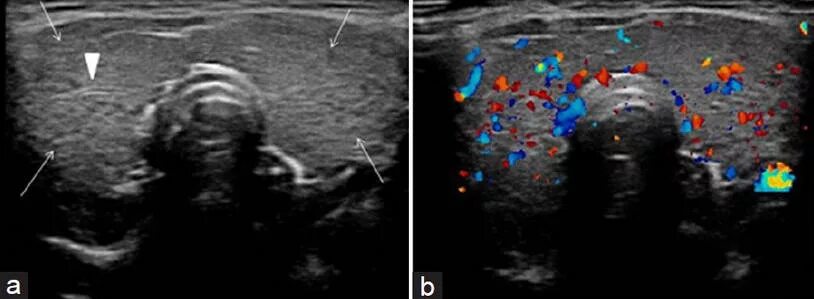

Диффузные изменения узлов щитовидной железы